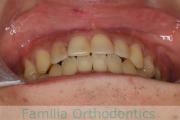

正面

左側